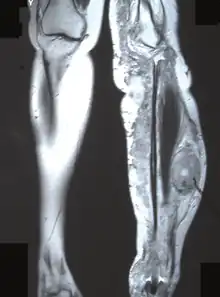

MRI (coronal plane) showing the site of MPNST in the left tibia.

Malignant peripheral nerve sheath tumour (MPNST)

(epithelioid and perineural subtypes)

Malignant 2–10% of soft tissue sarcomas. Epithelioid MPNST is particularly rare (~5% of all MPNST)

• Extremities, trunk, head, and neck area